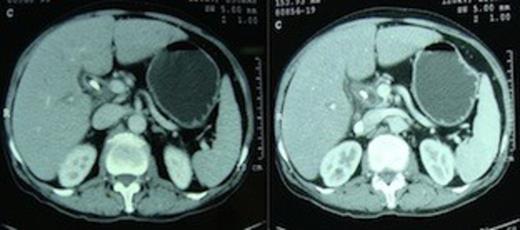

Computed tomography scan demonstrating absence of the body and tail of pancreas anterior to the splenic artery and vein.